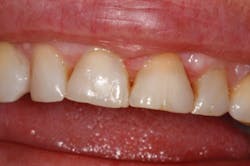

Figure 4: 30-days post-op

Solea's precision and ability to maintain a clean surgical site allowed this unscheduled procedure to be completed successfully. Additionally, rapid healing was observed (figure 3). With Solea, this was a minimally invasive procedure and crowns were prepared 30 days postoperatively (figure 5). Traditional surgery would require six to eight weeks until proper conditions were established for definitive restorative work. In addition, there would have been more postoperative pain and slower healing with traditional instruments.